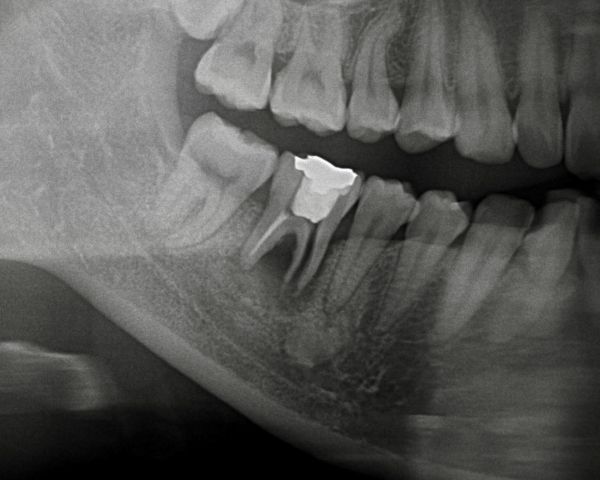

こちらがその時のレントゲン写真になります。

右下4番目と7番目の歯でブリッジが入っておりました。右下4番目の歯の周囲に薄く骨が溶けている像が見られました。

歯根破折(根のヒビ)を疑いましたが、マイクロスコープを用いても歯根破折を確認できなかったため、再根管治療(根の治療のやり直し)を行い、しばらく経過を見ました。